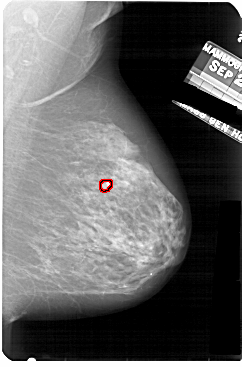

A_1859_1.LEFT_MLO

LEFT_MLO LINES 5191 PIXELS_PER_LINE 3736 BITS_PER_PIXEL 12 RESOLUTION 43.5 NON_OVERLAY

FILE: A_1859_1.RIGHT_MLO.OVERLAY

TOTAL_ABNORMALITIES 1

ABNORMALITY 1

LESION_TYPE CALCIFICATION TYPE PLEOMORPHIC DISTRIBUTION CLUSTERED

ASSESSMENT 4

SUBTLETY 4

PATHOLOGY BENIGN

TOTAL_OUTLINES 1

BOUNDARY